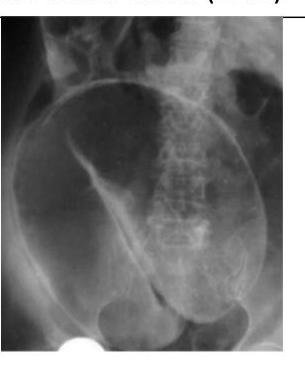

Contenido mejorado por IA (Markdown)

# VÓLVULO DE COLON ## DEFINICIÓN Un **vólvulo** se define como la torsión de un órgano a través de un eje, sobre su pedículo vascular. El vólvulo de colon típicamente resulta en una obstrucción intestinal en asa cerrada. La rotación del pedículo vascular y la dilatación del colon contribuye a compromiso de la perfusión del colon.  ## LOCALIZACIÓN 1. **SIGMOIDES** (la más frecuente) 2. Ciego (frecuente en mujeres de edad media)  # EPIDEMIOLOGÍA - Corresponde a 1 - 7 % de todas las oclusiones intestinales - Tasa de mortalidad 7 - 20 % - Es más común en América Latina, África y Europa del Este - En naciones de primer mundo es relativamente raro. - En esos países es la 3a causa de obstrucción de colon (después de neoplasias y enfermedad diverticular) ## FACTORES DE RIESGO CIEGO - Femeninos de edad media. - Cirugías abdominales previas - Adultos mayores con inactividad prolongada ## FACTORES DE RIESGO SIGMOIDES - Masculinos - Edad mayor 60 años - Pacientes adultos mayores institucionalizados - Estreñimiento crónico - Enfermedad neuropsiquiátrica - Retraso mental - Desórdenes neurológicos - Cirugías abdominales previas - Embarazo (**causa más frecuente de obstrucción**) - Infestación por gusanos redondos - Megacolon (Chagas y Hirschprung) ## CLINICA ## CUADRO DE OBSTRUCCIÓN INTESTINAL QUE CURSA CON DOLOR ABDOMINAL Y DISTENSIÓN (ASA CERRADA) ## - DOLOR ABDOMINAL - Distensión abdominal **SÚBITA Y ESPECTACULAR**. - Ausencia de canalización de gases - Ausencia de evacuaciones - Náusea y vómito - Hipersensibilidad abdominal - Resistencia muscular - Ruidos peristálticos de tono metálico - Fosa ilíaca izquierda vacía a la palpación abdominal **ISQUEMIA / PERFORACIÓN** Dolor Intenso + Irritación Peritoneal + Datos de Sepsis. - Ausencia de materia fecal en exploración rectal - Materia fecal melénica en el recto (poco común) # DIAGNÓSTICO Laboratorio: realizar BH, QS, ES y pruebas de coagulación en todos los sospechosos de Vólvulo. ## ESTUDIOS DE IMAGEN. ## RADIOGRAFÍA ABDOMEN - Permite diagnóstico en mayor porcentaje en los Sigmoides que en los Cecales - Solicitar de pie (buscando aire libre subdiafragmático = Perforación) y decúbito. - Realizarla en ausencia de TAC de urgencias ## Hallazgos Cecales: 1. Asa desproporcionadamente dilata y patrón de oclusión distal (91%) 2. Nivel hidroaéreo único en el ciego y colapso de colon distal (82%)  ## ENEMA DE BARIO - Es más útil en el sigmoides que en el cecal - Contraindicada en sospecha de peritonitis. - Realizarlo en sospecha de Vólvulo sigmoides cuya radiografía no sea concluyente o TAC no accesible. - Imagen en "pico de ave" o "as de espadas" en el punto del vólvulo sigmoides, producida por el medio de contraste en el enema de bario.  ## TOMOGRAFÍA COMPUTARIZADA Es el **ESTUDIO CON MAYOR PROBABILIDAD DIAGNÓSTICA** tanto en Sigmoides (89%) y Ciego (71.4%). ## Hallazgos Sigmoides - Signo del Grano de café + Nivel hidroaéreo único + Colapso de Colon Izquierdo - Signo del remolino (flecha roja) - - Distensión del ciego de +10 cm  # TRATAMIENTO SIGMOIDES ## MANEJO MÉDICO 1. REANIMACIÓN TEMPRANA: - Balance adecuado de líquidos y electrolitos - Apoyo ventilatorio (en caso necesario) - Descompresión Intestinal con **SONDA NASOGÁSTRICA** 2. ANTIBIÓTICOS: deben ser **amplio espectro** con cobertura anaeróbica en pacientes con peritonitis, isquemia o sepsis. 3. MONITORIZACIÓN URINARIA: si es necesario **SONDA URINARIA TRANSURETRAL** para adecuado control de líquidos. ## RESOLUCIÓN NO QUIRÚRGICA Posterior al diagnóstico de Vólvulo y dependiendo las condiciones del paciente, se puede realizar la destorsión y descompresión del vólvulo sin cirugía: ## 1ra elección: SIGMOIDOSCOPÍA O COLONOSCOPÍA DE EMERGENCIA. 1. El recto se insulfa para proporcionar buena visibilidad y facilitar el ápice del vólvulo. 2. Si la distorsión no ocurre, se introduce un tubo rectal suave dirigido bajo visión directa. 3. La punta del endoscopio puede ser utilizada con constante presión en el ápice del vólvulo. - Tasa de éxito de destorsión no quirúrgica 96 - 64 % (más exitosa en sigmoidoscopía rígida en comparación a colonoscopía. Recurrencia de 43 % en 32 días y 85 % en los siguientes 8 meses. ## POSTERIOR A LA REDUCCIÓN DEL VÓLVULO - PROGRAMAR Qx DEFINITIVA ELECTIVA. ## RESOLUCIÓN QUIRÚRGICA ## RESECCIÓN DE SIGMOIDES CON ANASTOMOSIS PRIMARIA ## CIRUGÍA ELECTIVA - Indicada de forma electiva o semielectiva a los pacientes con resolución no quirúrgica del vólvulo. - Se sugiere hacerla durante el mismo periodo de hospitalización. ## CIRUGÍA DE URGENCIA - Pacientes con vólvulo con evidencia de **PERITONITIS, ISQUEMIA O NECROSIS** o cuando el tratamiento no quirúrgico no resulta exitoso. - COLECTOMÍA TOTAL - indicada en megacolon o megarrecto asociado a vólvulo sigmoides. # TRATAMIENTO CIEGO ## 1ra elección: MANEJO QUIRÚRGICO. - Valorar edad, condición, presencia de comorbilidad grave y el estado de la pared del ciego. - Examinar el colon distal en el transoperatorio en búsqueda de una oclusión distal como posible causa. RESECCIÓN DEL VÓLVULO CECAL + HEMICOLECTOMÍA DERECHA + ANASTOMOSIS PRIMARIA - Alternativa: Ileostomía + Fístula mucosa distal DESTORSIÓN + CECOPEXIA - Indicada en pacientes con alto riesgo de morbimortalidad para resección segmentaria # ALGORTIMO MANEJO DEL VÓLVULO